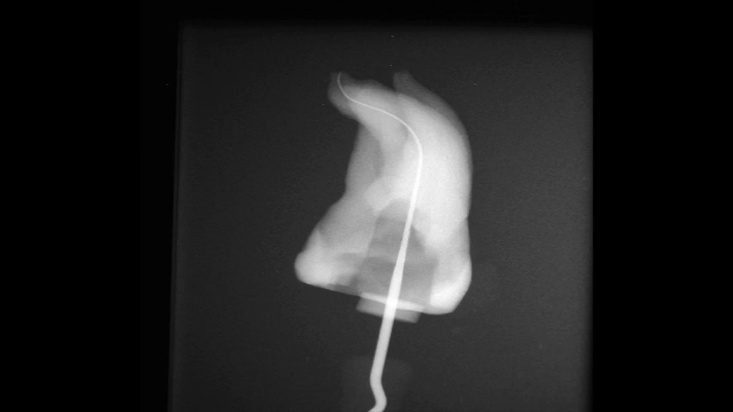

Сл. 19.10 а) Палатиналниот канал е пронајден со К-турпија #0,08.